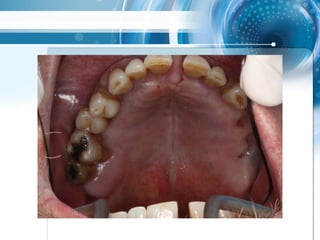

• Multiple Änderungen von Modellsituation nach CT

scan, Extraktionen und Wurzelfüllungen realisiert,

4 geplante Extraktionen

Triple scan Technik

Triple scan Technik •Multiple Änderungen von Modellsituation nach CT scan, Extraktionen und Wurzelfüllungen realisiert, 4 geplante Extraktionen

• 54.

• 55.

• 56.

• 57.